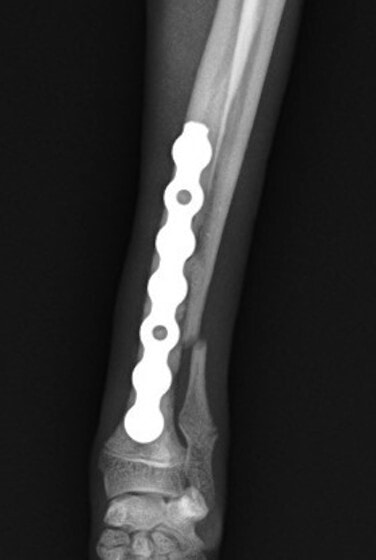

トイプードル 右遠位橈尺骨短斜骨折のALPSによる内固定